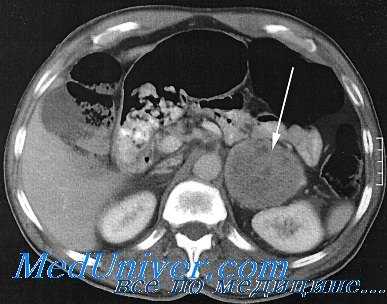

- Методы инструментальной диагностики. С целью топической диагностики феохромоцитомы выполняются УЗИ надпочечников и томография (КТ или МРТ) надпочечников, экскреторная урография, селективная артериография почечных и надпочечниковых артерий, сцинтиграфия надпочечников, рентгеноскопия или рентгенография органов грудной клетки (для исключения внутригрудного расположения опухоли). Изменения на ЭКГ неспецифичны, разнообразны и обычно носят временный характер, обнаруживаясь во время приступов.

Для визуализации феохромоцитомы применяется компьютерная томография (КТ) и магнитно-резонансная томография (МРТ).

- Топическая диагностика: КТ (при хромаффинных опухолях органов грудной клетки, брюшной полости и малого таза), МРТ (при параганглиомах головы и шеи, а также при противопоказаниях к лучевой нагрузке).

УЗИ, сцинтиграфия, компьютерная томография, магнитно-резонансная томография надпочечников – определяется плотное образование округлой или овальной формы с четкими границами различного размера с и без очагов некроза и кальцификатов [3].